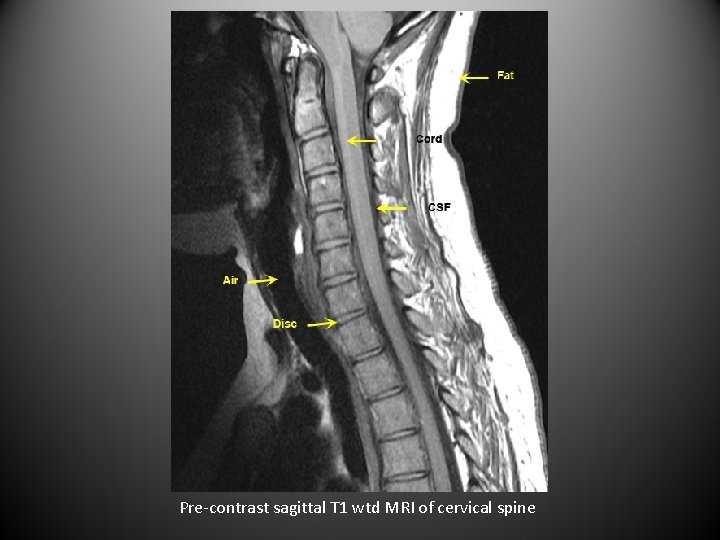

Spinal cord anatomy

Pre-contrast sagittal T 1 wtd MRI of cervical spine